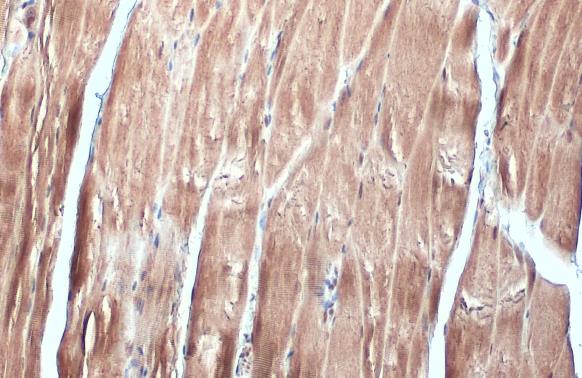

FBXL17 antibody [C1C3] detects FBXL17 protein at cytoplasm and nucleus by immunohistochemical analysis.

Sample: Paraffin-embedded mouse muscle.

FBXL17 stained by FBXL17 antibody [C1C3] (GTX119211) diluted at 1:500.

Antigen Retrieval: Citrate buffer, pH 6.0, 15 min